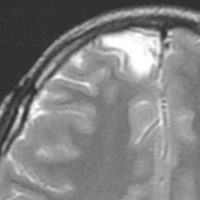

画像診断

- とても難しいといえます,特徴的な所見がないからです

- ほとんどが髄膜に接する脳表を巻き込む病変なのです

- 小さな多房性のう胞を伴ったり,脳内に結節とのう胞を形成するものもあります

- T1強調では等信号から低信号

- T2強調画像では低信号領域と血管のflow-voidがみられます

- ガドリニウム増強では不規則な増強像を見ることが多いです

- T2低信号の部分(結節)が強くガドリニウム増強されることも特徴かもしれません

難治性てんかんで発症した小児ですが,どう見てもDNTなのかなと思います。石灰化もありません。一般的に,meningioangiomatosisの術前診断は困難であると言えます。いずれにしても治療はlesionectomyです。